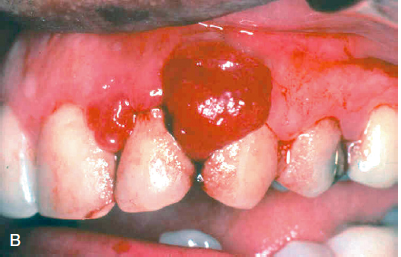

What are oral pyogenic granulomas?

oral masses usually found on the gingiva of children, young adults, and pregnant women. These lesions are highly vascular and often erythematous appearing.

These tend to grow fastly but are typically benign and surgical excision is curative